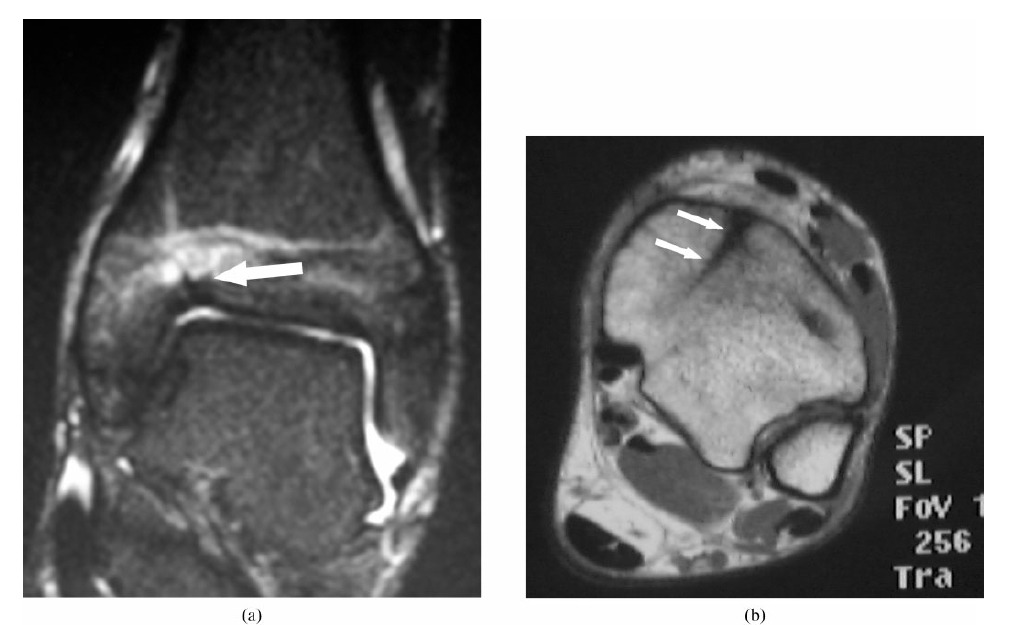

Trevor’s disease